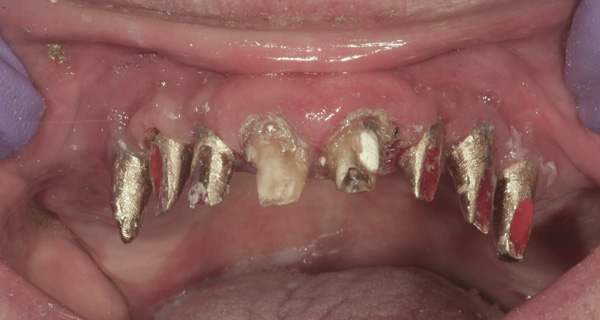

Background: This patient had a failing maxillary dentition and refused to wear a removable prosthesis. A staged approach was employed to retain some of his natural tooth abutments, and recession was noticed at the time of the impression for the second group of implants. Figure 1 shows the patient following insertion of the first set of implant custom abutments; the adjacent natural teeth are still present to support the provisional bridge. Seven months later, as shown in Figure 2, those first-stage custom abutments exhibited evidence of 1 mm to 3 mm of recession.

Results: A decision was made to re-prepare all of the abutments intraorally (Figure 3) so that all abutment margins would be at or below the gingival margin. (Of note, tooth Nos. 8 and 9, also shown in Figure 3, were later submerged for the case to be fully implant-supported.) While re-preparation greatly improved the esthetics of the final result, it required retraction cord placement, new impressions, and new castings.

Figure 2 After 7 months, the first-stage custom abutments exhibited evidence of 1 mm to 3 mm of recession.

Figure 2

Figure 3 Abutments re-prepared intraorally.

Figure 3